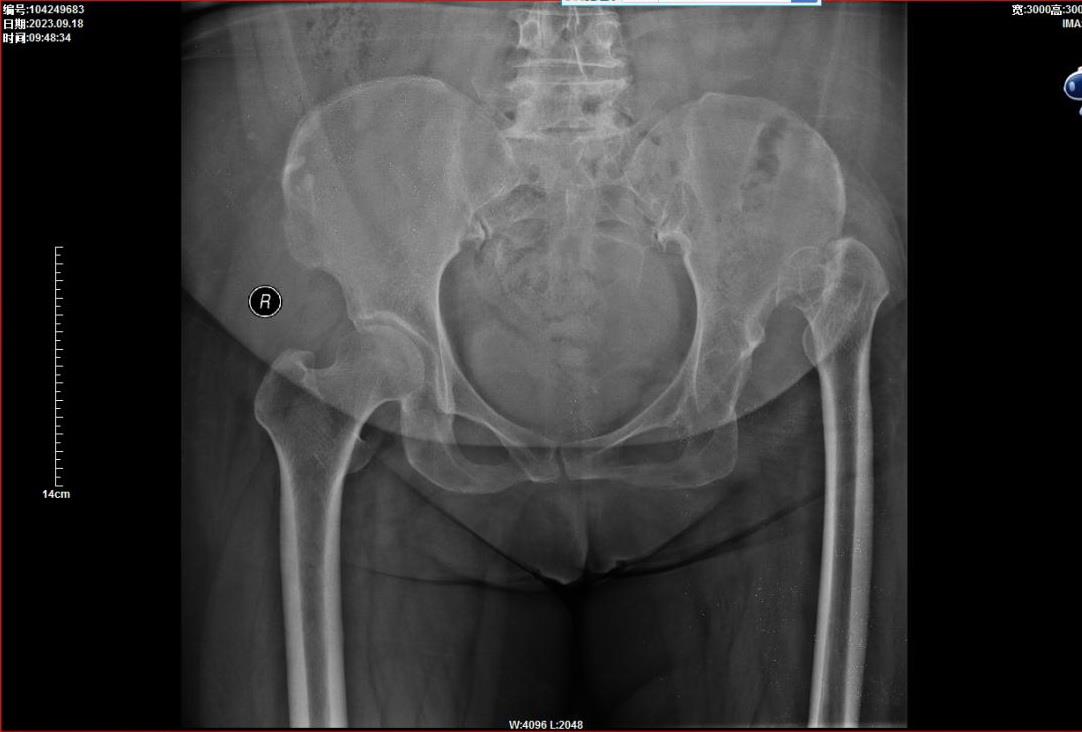

2023年9月18号,市中医院骨伤四科迎来了一位特殊的女性病人,她54岁,先天性残疾,从小就一条腿长,一条腿短,走路摇摇摆摆。就这样在周围人异样的目光中慢慢长大,直至年过半百。近年来髋部疼痛越来越剧烈,每迈出一步都非常痛苦,最终因为再也无法忍受病痛的折磨,找到了六安市中医院骨伤四科张弢主任。

经查这位病人患的是先天性髋关节脱位,股骨头上移,股骨头和髋臼都没有正常发育,处于幼稚状态,患肢短缩约7厘米,没有得到过有效治疗。